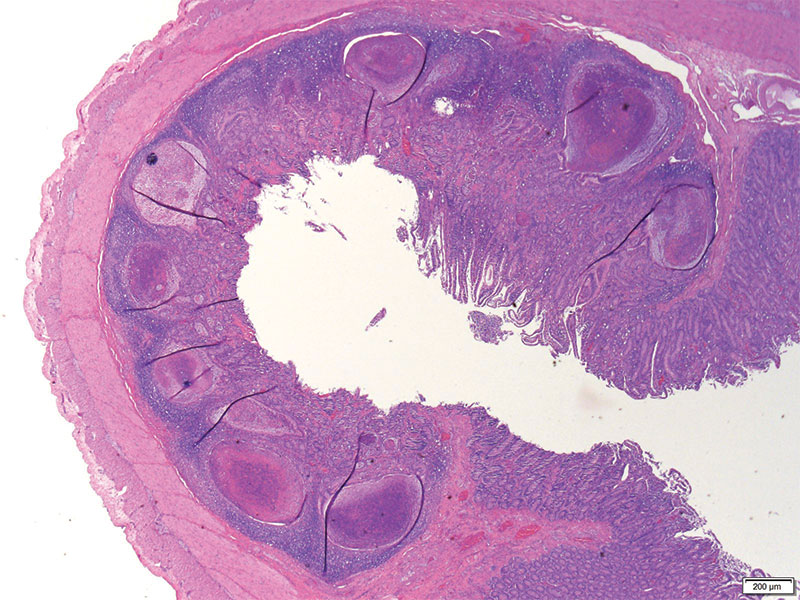

En este caso en particular, nos enviaron muestras de heces y de la necropsia, con un historial completo y signos clínicos. Los hallazgos de Pohly, basados en pruebas de reacción de polimerasa en cadena (PCR), cultivos y análisis microscópico, revelaron lesiones causadas por Yersinia en el intestino. Yersinia es una bacteria normal en el intestino bovino y se incrementa como infección secundaria. También pueden ocurrir co-infecciones con patógenos como coccidios intestinales y Giardia, que se encontraron en un número alto en las muestras enviadas. Resultó interesante que las lesiones de Yersinia se parecen a las del virus de la diarrea viral bovina, aunque con diferencias sutiles. Por lo tanto, realizar un análisis para descartar ese virus es crucial, porque generalmente está ausente del intestino bovino. Con estos hallazgos, el veterinario del hato pudo trabajar con el productor, para optimizar tratamiento, prevención y manejo ambiental, disminuyendo la exposición a coccidios y Giardia, mejorando así la salud del hato.